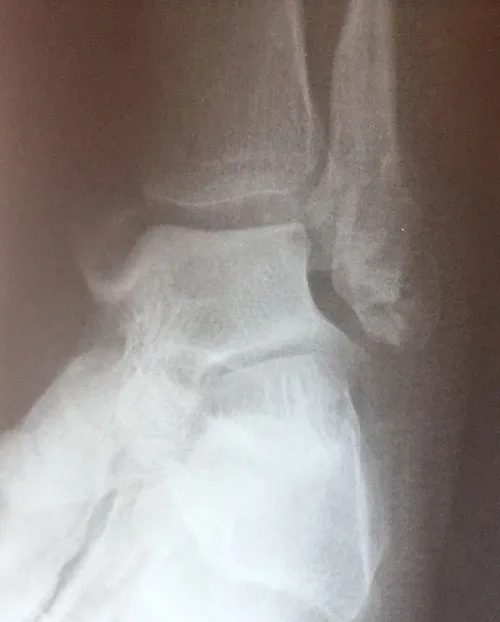

CT scan and Xray sagittal views of severly displaced posterior tibial malleolar fracture with comminution. This type of injury can cause significant problems in the future with disability if not treated with surgery to reduce the fracture and fixate.

Trimalleolar fractures involve fracture of the medial and lateral malleoli

along with a fracture of the posterior lip of the tibial

plafond; (posterior malleolar fracture). Fracture results from avulsion

by the posterior tibiofibular ligament at its site of attachment to the

tibia. The irregularity in the tibial articular surface of the tibia is

brought against the weightbearing surface of the talus and with

motion and weightbearing severe DJD develops.